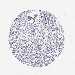

LIVER CANCER - Protein expressioni

A mouse-over function shows sample information and annotation data. Click on an image to view it in a full screen mode. Samples can be filtered based on level of antibody staining by selecting one or several of the following categories: high, medium, low and not detected. The assay and annotation is described here.

Note that samples used for immunohistochemistry by the Human Protein Atlas do not correspond to samples in the TCGA dataset.

Antibody stainingi

Antibody staining in the annotated cell types in the current human tissue is reported as not detected, low, medium, or high, based on conventional immunohistochemistry profiling in selected tissues. This score is based on the combination of the staining intensity and fraction of stained cells.

Each image is clickable and will lead to virtual microscopy that enables deeper exploration of all samples and also displays staining intensity scores, fraction scores and subcellular localization as well as patient and tissue information for each sample.

Antibody HPA050118

Antibody HPA056084

Antibody CAB012444

Staining

High

Medium

Low

Not detected

Intensity

Strong

Moderate

Weak

Negative

Quantity

>75%

75%-25%

<25%

None

Location

Nuclear

Cytoplasmic/membranous

Cytoplasmic/membranous,nuclear

Carcinoma, Hepatocellular, NOS

Cholangiocarcinoma